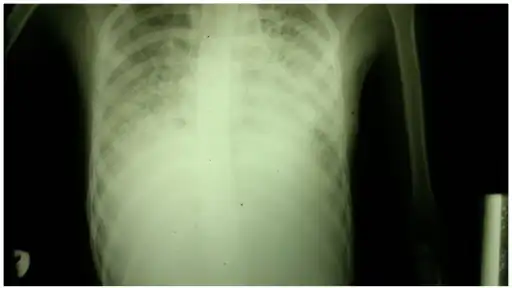

A chest X-ray demonstrating pulmonary fibrosis due to amiodarone

Pulmonary function testing